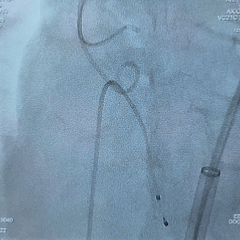

术中影像

根部造影

瓣叶活动差,可见明显反流,猪尾导管测量跨瓣压差约50mmHg

20mm球囊预扩

微腰微漏,左右冠均显影

造影确认瓣环与瓣膜位置

瓣膜0位初始定位释放,展开过程微微下移